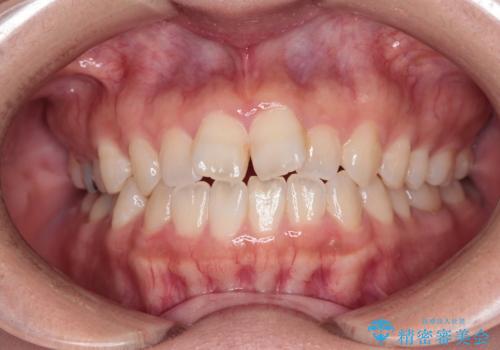

[マウスピース矯正] がたがたの歯並びをきれいにしたい

![[マウスピース矯正] がたがたの歯並びをきれいにしたいの症例 治療前](https://seimitsushinbi.jp/wp/wp-content/uploads/2025/06/0d238550c8a0fddc4de7b2c337c6c786-500x350.jpg?v=1750323380)

![[マウスピース矯正] がたがたの歯並びをきれいにしたいの症例 治療後](https://seimitsushinbi.jp/wp/wp-content/uploads/2025/06/IMG_0002-2-500x350.jpg?v=1750323305)